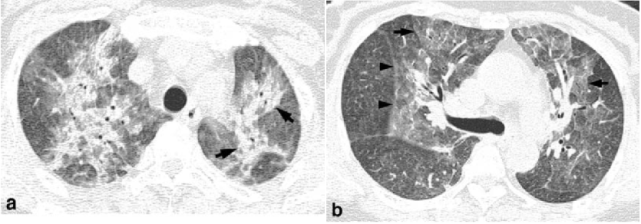

图 9. 57 岁女性肺炎支原体肺炎的胸部 CT:a.高分辨率 CT(1.25 mm 层厚)的肺窗图像显示弥散和斑片状的支气管周围区域,融合性结节或实变与双肺上叶中的周围磨玻璃样密度影。注意不透明的小叶分布,在正常和异常的肺小叶之间有明显的分界(箭头);b.在右主支气管获得的肺窗图像显示双肺上叶中的斑片状周围磨玻璃样密度影。注意小叶间隔增厚(箭头)与小叶分布的磨玻璃样密度影。右侧小裂隙(箭头)升高,表明右上叶体积减小。